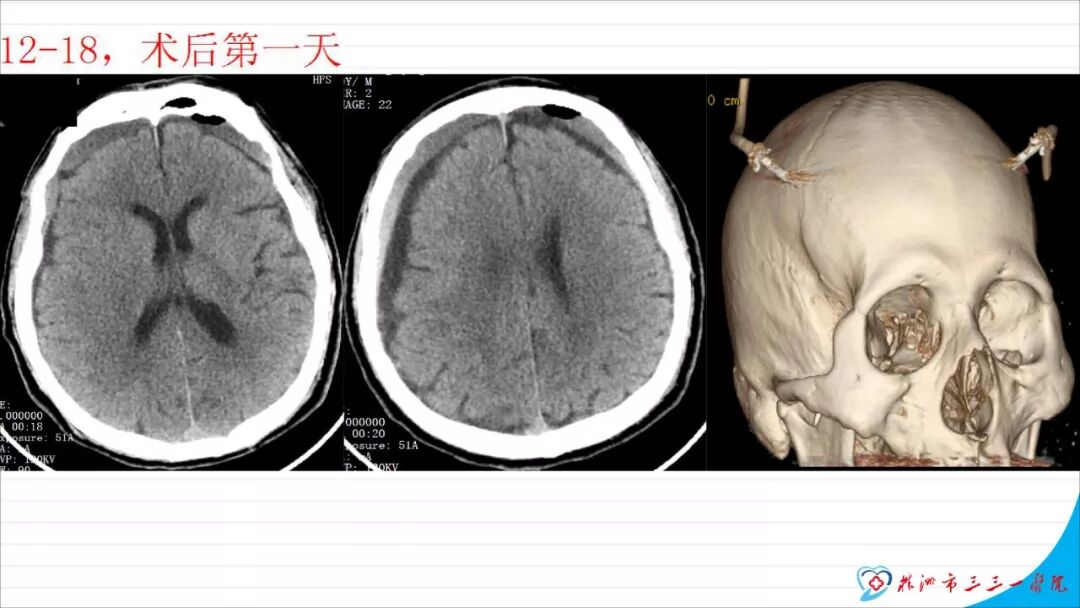

今天为大家分享的是《颅脑创伤-神经重症病例周刊》第113期,由株洲市三三一医院神经外科毛德龙医师带来的:老年病人慢性硬膜下血肿自然演变一例 ,天津医科大学总医院神经外科副主任兼NICU主任、“神外资讯中国颅脑创伤-神经重症专家组”委员江荣才教授对病例作出了精彩点评,欢迎观看、阅读。